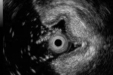

消化道早癌的微创克星

2026-04-02|消化中心内镜诊疗科 -